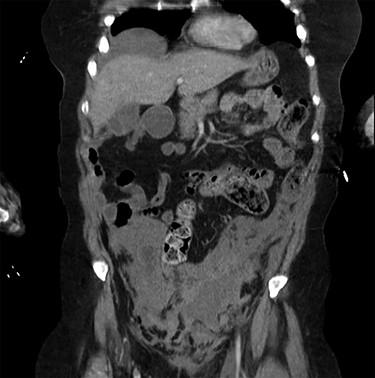

A 60-year-old Caucasian female was referred by her GP for a 2-day history of pain and swelling of the left leg. On examination, there was obvious limb swelling and a mass in the left iliac fossa. Soon after the presentation, the patient became hypotensive and arrested requiring cardiopulmonary resuscitation (CPR). The initial working diagnosis was PE secondary to DVT. Baseline investigations were normal but arterial blood gases showed compensated metabolic acidosis. After resuscitation, an urgent CT of abdomen, pelvis and chest was organized; this confirmed DVT of the left common iliac vein and also a large left adnexal mass with minimal ascites (Fig. 1). The patient, evidently in hypovolemic shock, was transferred for urgent exploratory laparotomy. She was found to have a large retroperitoneal haemorrhage with blood welling from the region of left iliac vessels. Proximal and distal control of iliac artery and vein was gained by tape and clamps allowing perioperative hypotension to improve. The vascular surgeon was called for help from the nearest tertiary centre. Upon further dissection, in the presence of the vascular surgeon, bleeding was noticed around the left common iliac vein, coming from the severed collaterals; these were eventually controlled with 6/0 prolene sutures. As the source of bleeding was not very clear, an opinion from vascular radiologist was sought. Review of the CT suggested that bleeding was likely to represent spontaneous rupture of venous collaterals due to DVT in the left iliac vein, secondary to MTS (Fig. 2). The patient was transferred to ITU with plans for relook surgery in next 48 hours once she had recovered from the acute insult. Unfortunately, the patient died the next day due to multi-organ failure and DIC secondary to massive transfusion.

Axial sections of the CT scan showing the thrombosed external iliac vein (I.V.) and the pelvic haematoma.